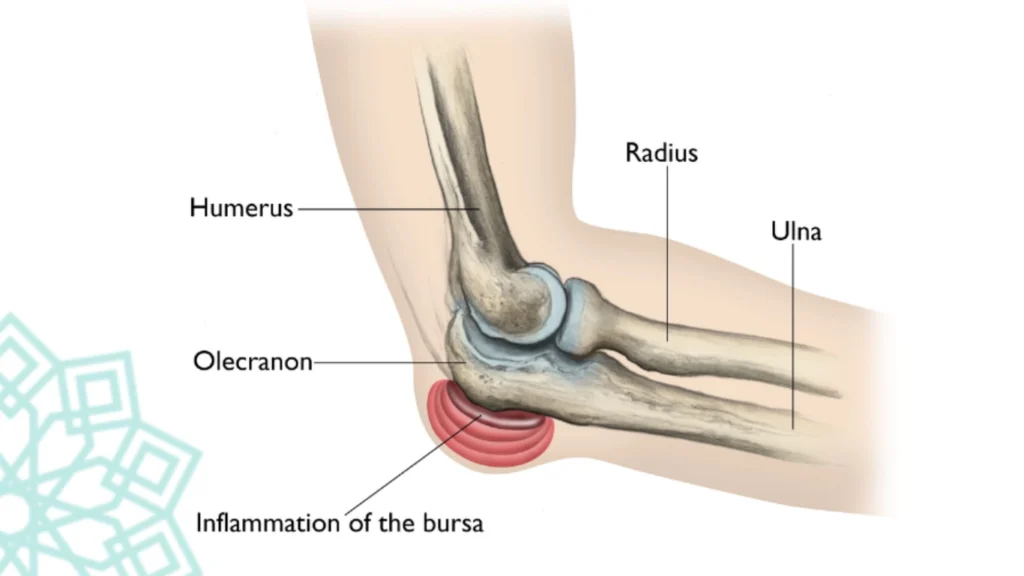

The olecranon bursa is a small, fluid-filled sac at the back of the elbow. Its main role is to cushion and reduce friction between the skin, bones, and tendons during movement. When this bursa becomes inflamed or irritated, it fills with excess fluid, resulting in visible swelling, pain, and tenderness.

This condition is sometimes nicknamed “Popeye Elbow” due to the round, swollen appearance at the elbow tip.